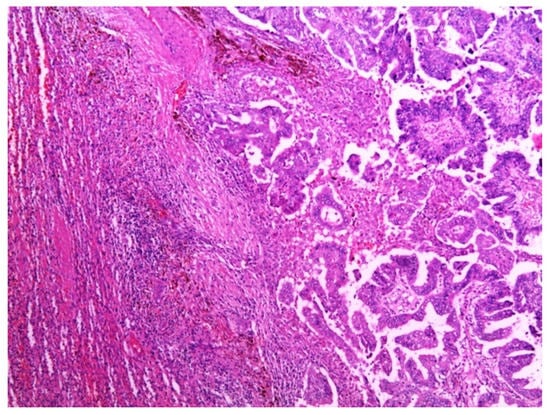

2. Case Presentation

3. Multidisciplinary Expert Consultation and Final Diagnosis

4. Treatment